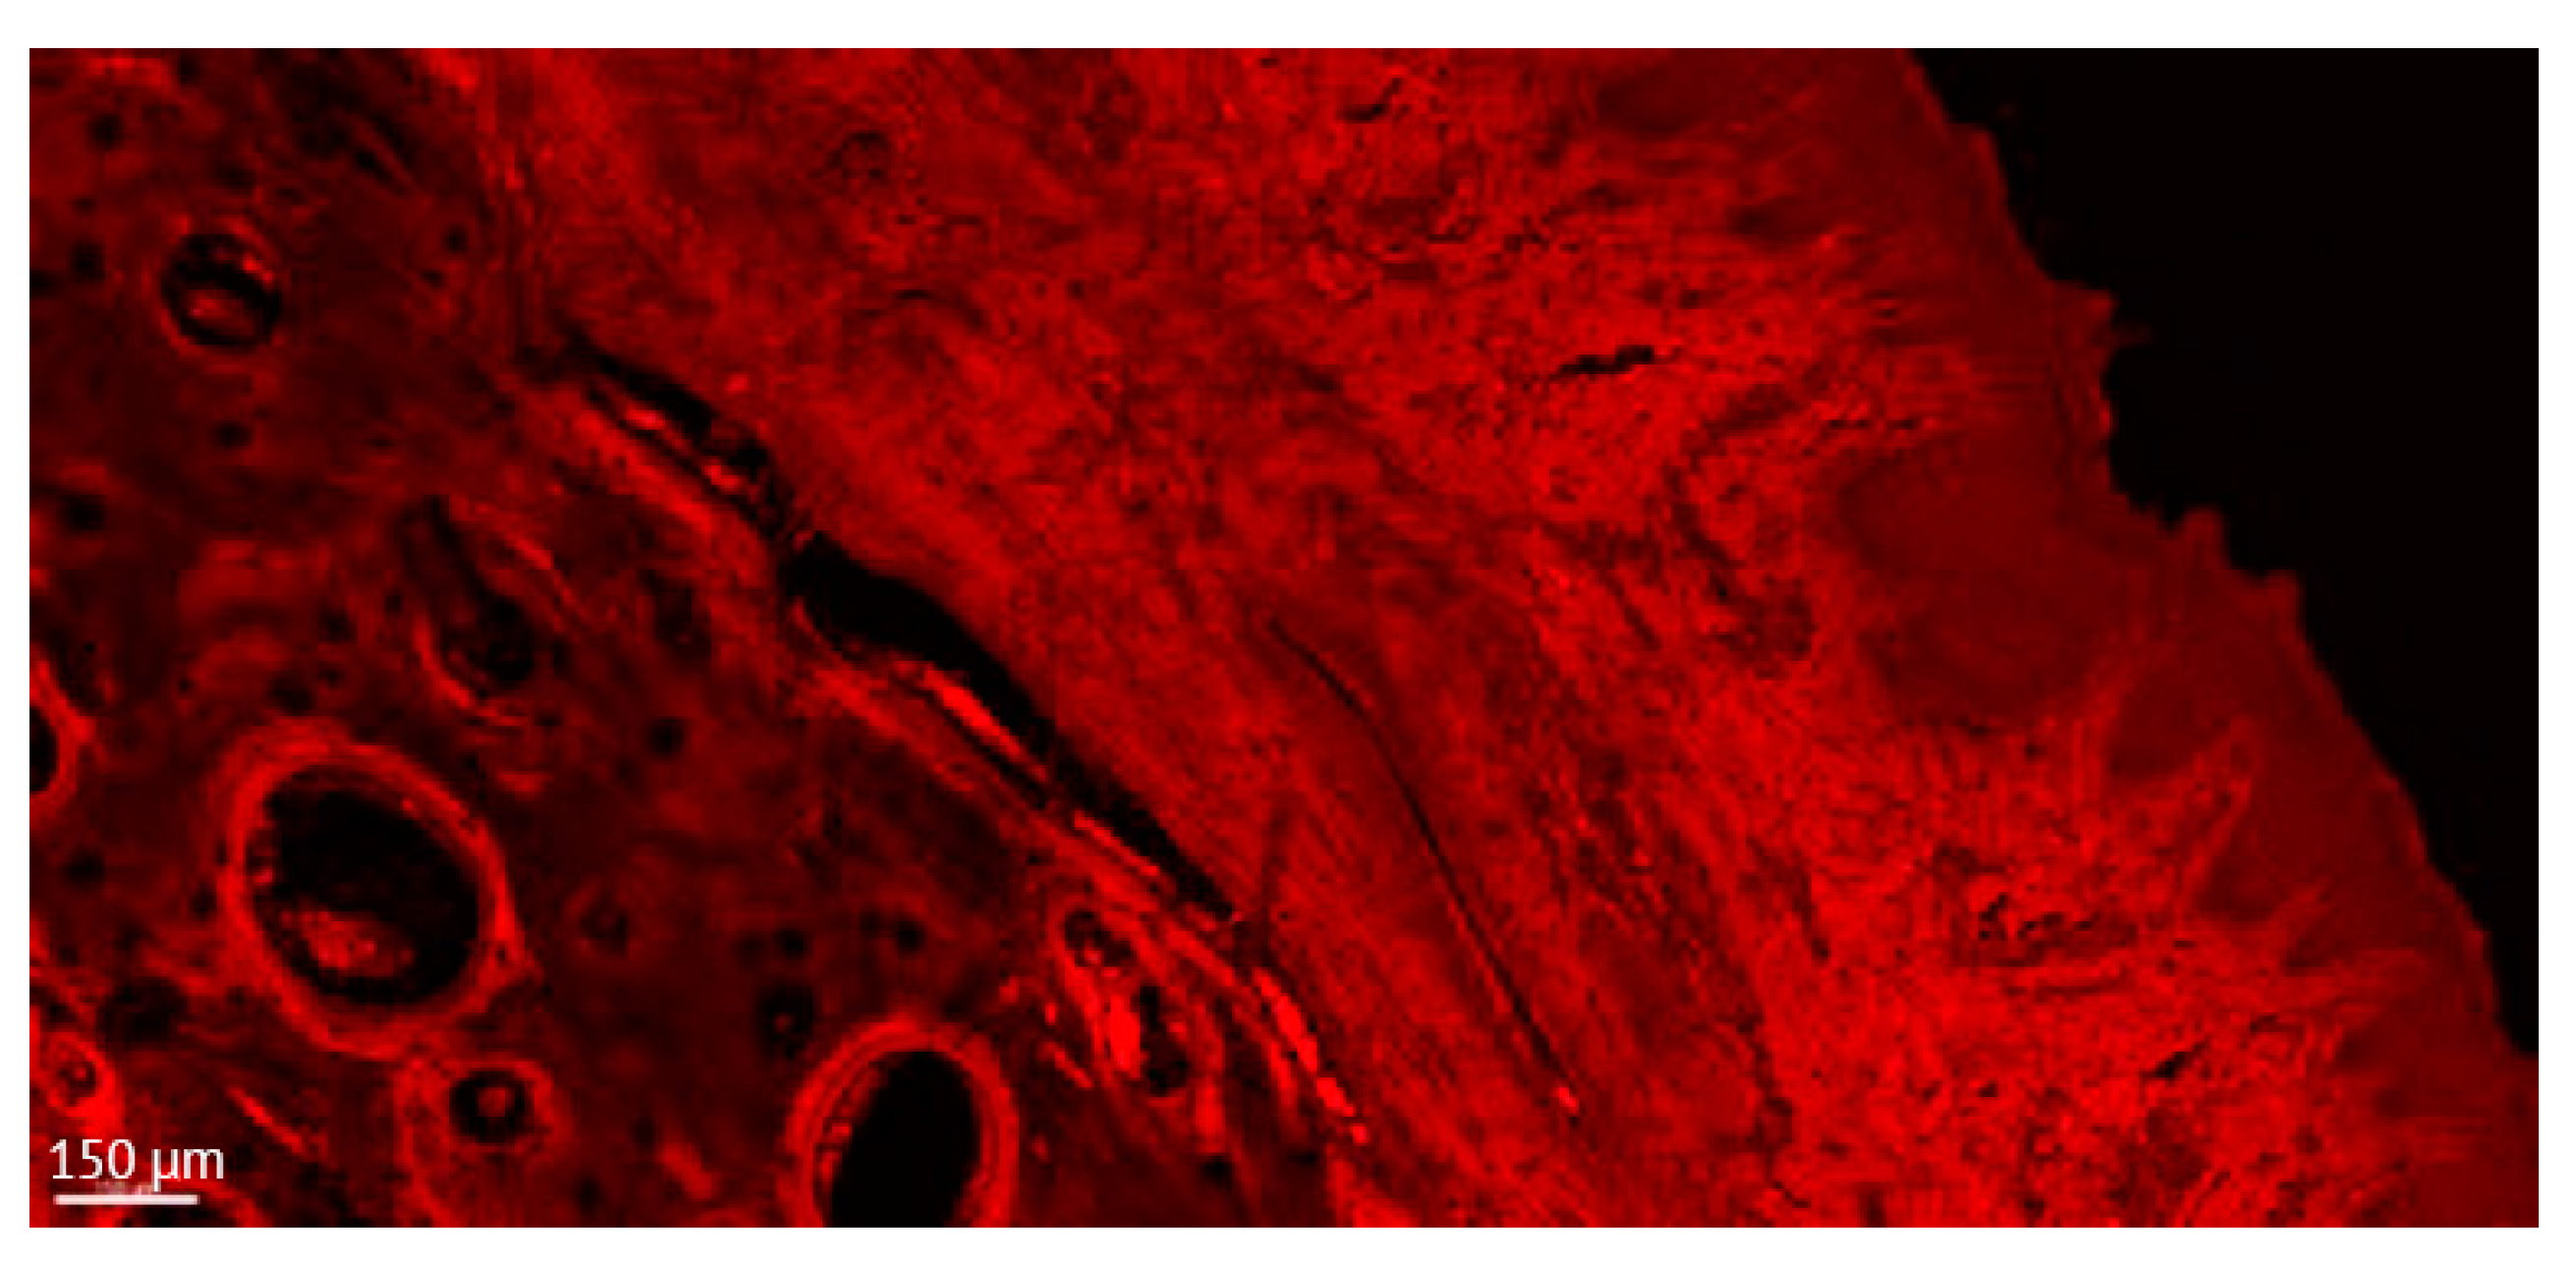

3.1.1. Qualitative Comparison between the Light Microscopy, CLSM Thin, and CLSM Thick Sections

3.1.2. 3D Reconstruction Analysis